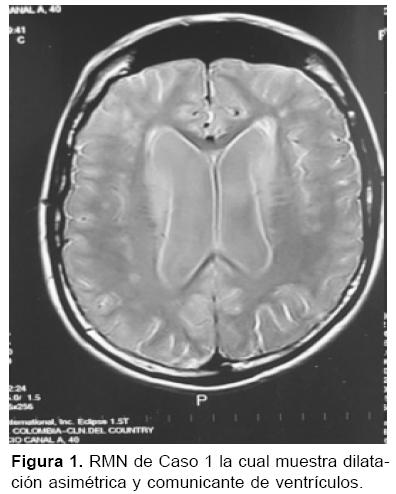

Paciente masculino de 44 años de edad, administrador hotelero, quien inicia cuadro clínico de cuatro años de evolución con síntomas neurológicos consistentes en ideas megalomaníacas, pérdida de memoria reciente, insomnio y ansiedad; para esa época se toma resonancia magnética (RM) cerebral que fue informada como normal. Seis meses después presenta comportamiento pueril y comienza con pérdida de funciones mentales superiores (alteración cognoscitiva, juicio, raciocinio, abstracción, cálculo), se realiza nueva RM que muestra dilatación ventricular sin efecto compresivo figura 1. En abril del 2001 por persistencia y empeoramiento de la sintomatología, se realiza punción lumbar con estudio de líquido cefalorraquídeo (LCR) que muestra: presión de apertura 13 cm, leucocitos 0, eritrocitos 0, glicemia 51 mg/dl (76), proteínas 4 g/dl, tinta china (-), VDRL (+) 1: 16 con FTA-ABS (+); ante lo cual el paciente es tratado con penicilina cristalina por 24 días con diagnóstico de neurosífilis. Se realizaron, además, anticuerpos antinucleares (ANA) que fueron positivos a 1: 40 con patrón granular, anticardiolipinas IgG 40 GPL e IgM mayor a 200 MPL, anti-ß2 glicoproteína I (-) y ecocardiograma normal.

El paciente persiste con sintomatología y empeoramiento de sus funciones mentales superiores; además, ausencia de control de esfínteres, marcha atáxica y alteración cognoscitiva. Se repite RM cerebral que muestra gran dilatación de ventrículos con efecto compresivo incipiente; se realiza prueba de LCR para determinar hidrocefalia de presión normal, la cual fue positiva; ante lo cual se decide derivación ventrículo-peritoneal con una respuesta favorable y mejoría parcial de su cuadro neurológico (control de esfínteres y marcha atáxica). Se repite estudio de cardiolipinas que muestra IgG de 84 GPL e IgM de 385 MPL (junio 2002). Se inicia tratamiento con asa 100 mg/día y clopidogrel 75 mg/día, con lo que presenta estabilización y leve recuperación de su sintomatología.